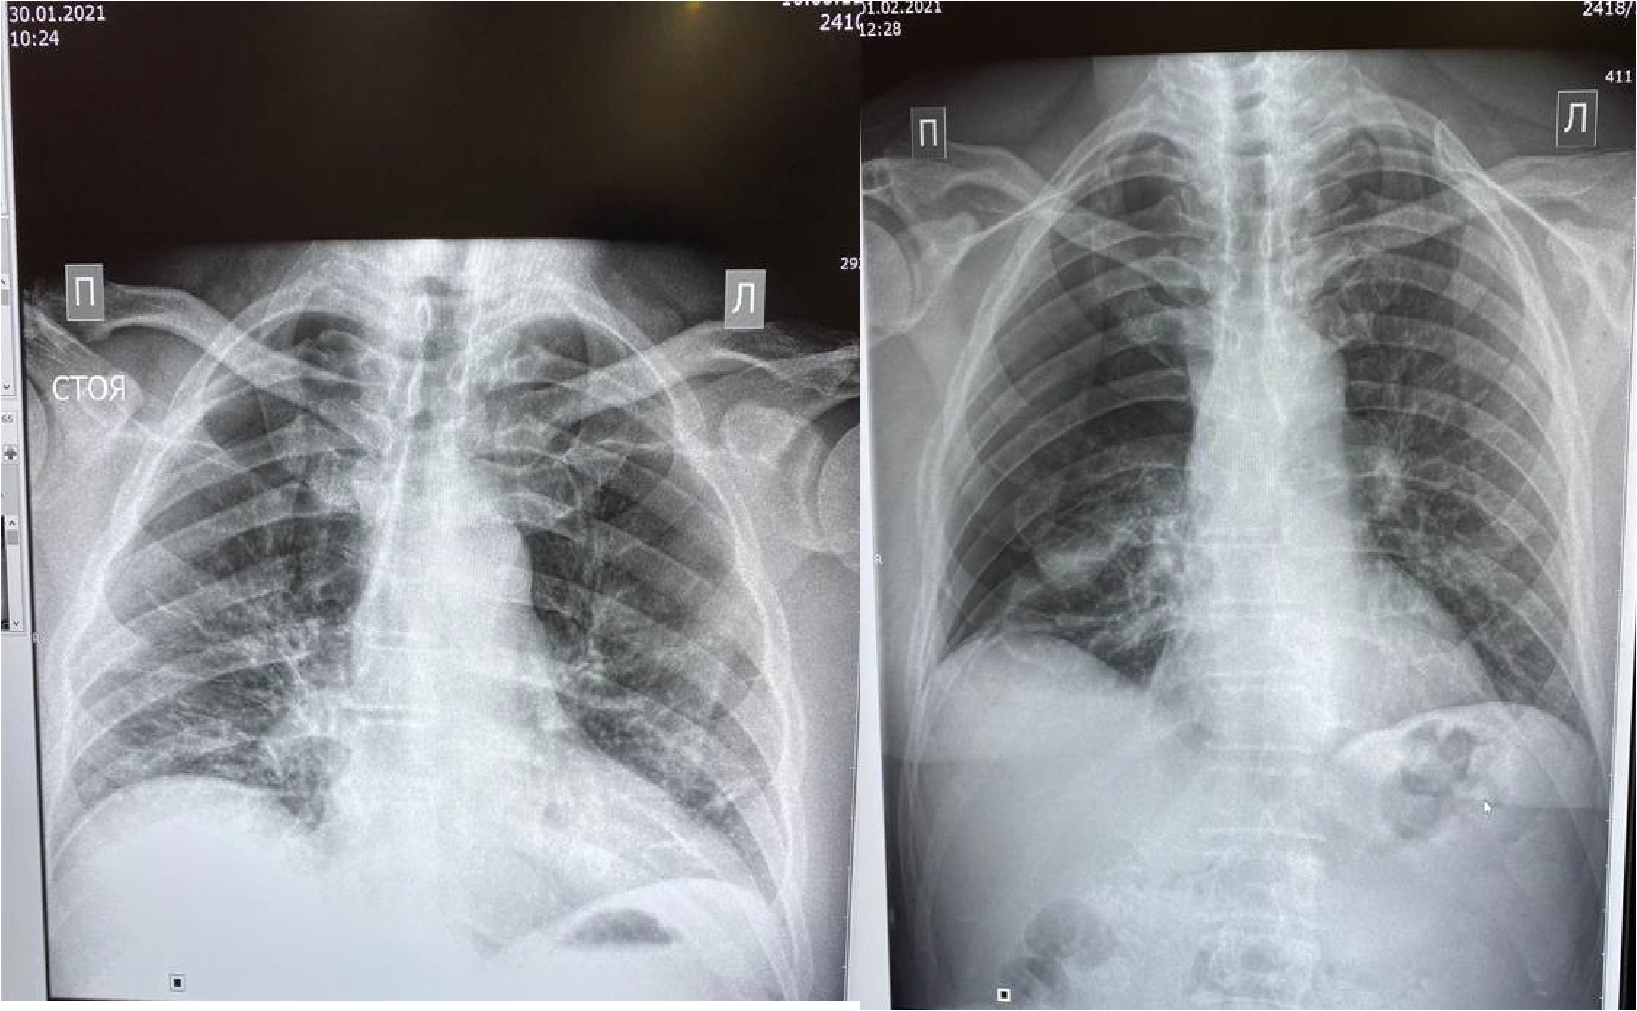

Рисунок 6. Рентгенограмма органов грудной клетки – признаки двусторонней полисегментарной интерстициальной пневмонии (объем поражения 30%, КТ-2). Верхушечный правосторонний пневмоторакс

Проведено дренирование плевральной полости справа по Бюлау. В результате отмечена отчетливая положительная динамика в виде устранения одышки, повышения SpO2. Через 3-е суток при контрольной рентгенографии органов грудной клетки выявлен верхушечный пневмоторакс справа (рис. 6), проведена пункция плевральной полости, дренирование продолжено. На фоне устойчивой положительной динамики в дальнейшем, на 23-е сутки терапии пациент выписан в удовлетворительном состоянии.